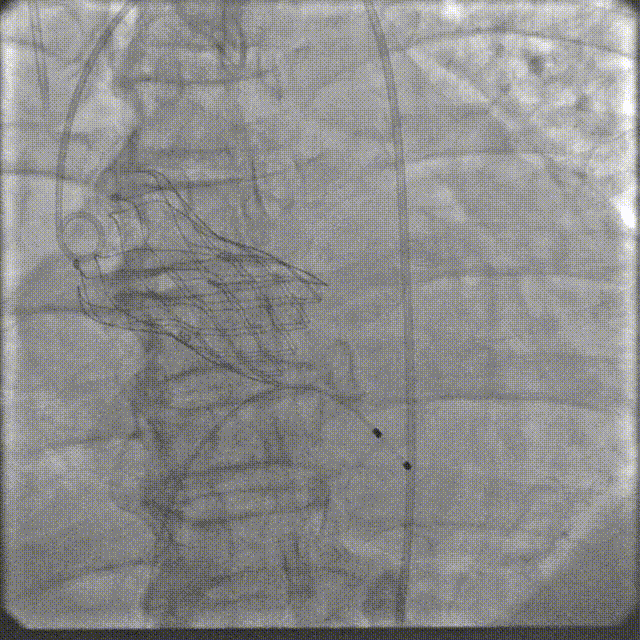

3月30日上午,培训班在重大疾病新药靶发现及新药创制全国重点实验室模式动物工程研究中心开展TAVR手术实操训练,二尖瓣缘对缘修复术器械演示。全体学员在符合GLP标准的实验环境中,使用经病理建模的实验猪进行介入操作演练。该动物模型通过专业培育,其主动脉瓣钙化程度与血流动力学参数可复现人类重度主动脉瓣狭窄的核心病理特征。

在数字减影血管造影(DSA)与经胸超声(TTE)双模影像引导下,学员系统完成经导管主动脉瓣置换术全流程操作:首先建立经皮腹主动脉穿刺入路,随后进行导丝跨瓣定位,继而操控人工瓣膜输送系统,最终实现瓣膜精准释放。训练重点强化三个技术维度:①血管入路建立与并发症预防 ②影像引导下的器械递送路径规划 ③基于实时超声的血流动力学评估。

通过标准化动物实验平台,参训医师不仅掌握了TAVR手术的核心操作规范,更深入理解了影像学参数与解剖结构动态匹配的决策逻辑。该训练体系通过量化评估穿刺成功率、瓣膜定位精度及操作时效性等核心指标,为临床技术转化建立可追溯的质量控制标准。